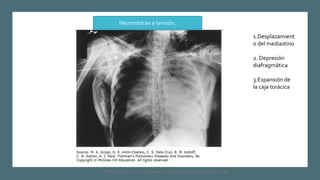

1.Desplazamient

o del mediastino

2. Depresión

diafragmática

3.Expansión de

la caja torácica

Neumotórax a tensión.